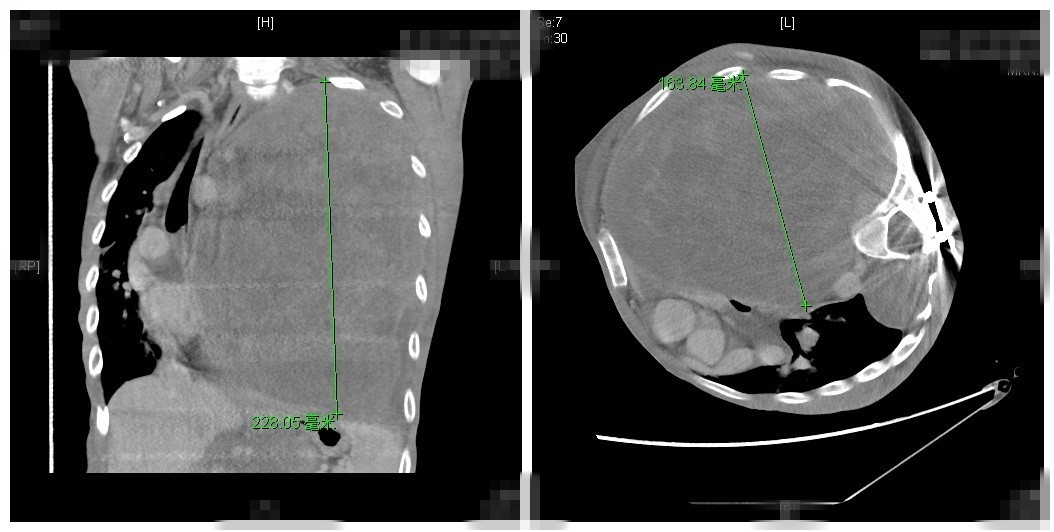

图为小飞术前肿瘤CT影像

小飞的胸部CT提示:肿瘤在胸腔内已达22.8*16.3cm。“相当于在胸腔里占据了1.5个肺脏的位置。”胸外科陈东红医师说。接收一个重症的患者,救命和保命将是一项系统的工程。由副院长王劲主持,胸外科、神经外科、麻醉科、重症监护室、输血科、影像科联合病例讨论,诊断患者为神经纤维瘤病Ⅰ型(以下简称“NFⅠ”),同时达成共识,虽手术风险极高,但却是唯一的希望。NFⅠ是一种常染色体显性遗传的家族性疾病,由肿瘤抑制基因突变而致。2006年,据约翰霍普金斯大学研究者报道,NFⅠ发病率为1:2 500~1:3 300。